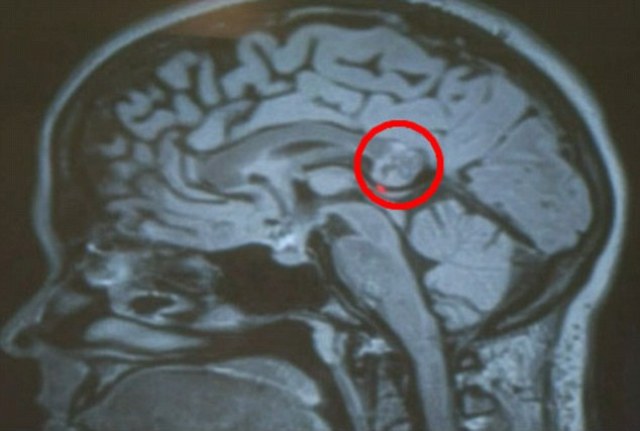

Խնդրի պատճառը պարզելու նպատակով Յամինին դիմել է Լոս Անջելեսի Գանգի հիմքի վիրաբուժության կենտրոնի բժիշկ Հրայր Շահինյանին, ով կնոջ մոտ ախտորոշել է գլխուղեղի ուռուցք: Հետազոտելով ուռուցքի բնույթը՝ բժիշկը որոշում է կայացրել հեռացնել այն՝ դիմելով միկրոսկոպիկ վիրահատության: Սակայն վիրահատության ընթացքում Հ. Շահինյանը, ով մոտ 7 հազ ուռուցք է հեռացրել, եկել է անակնկալի, քանի որ ուռուցքի փոխարեն կնոջ ուղեղում հայտնաբերել է տերատոմա՝ ոսկրեր, ատամներ և նույնիսկ մազեր ունեցող Յամինիի երկվորյակ քրոջը:

«Պարզվեց՝ սա իմ «հրեշ» քույրն էր, ով 26 տարի տանջել է ինձ», - վիրահատությունից հետո ասել է Յամինին: